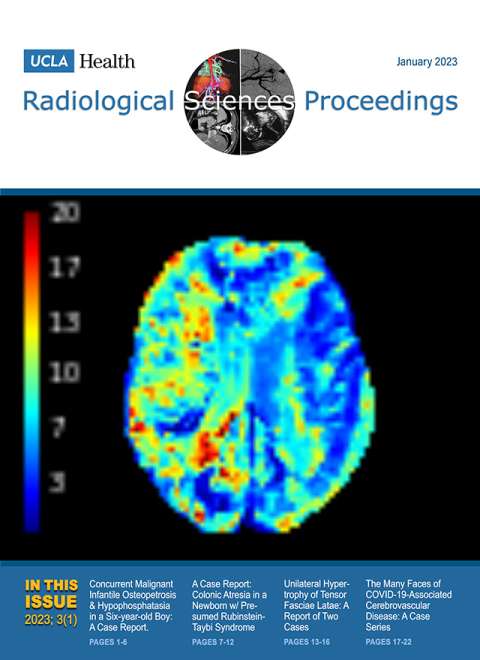

January 2023

Volume 3, Issue 1

- Concurrent Malignant Infantile Osteopetrosis and Hypophosphatasia in a Six-year-old Boy: A Case Report

- A Case Report: Colonic Atresia in a Newborn with Presumed Rubinstein-Taybi Syndrome

- Unilateral Hypertrophy of Tensor Fasciae Latae: A Report of Two Cases

- The Many Faces of COVID-19-Associated Cerebrovascular Disease: A Case Series